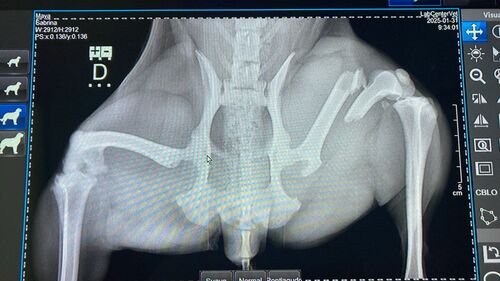

Contudo, na manhã do dia 31 de janeiro, Maya quebrou o fêmur da perna traseira esquerda. Para realizar a cirurgia, precisamos de R$3.500,00. Conseguimos negociar os outros gastos, como a consulta inicial, mas a cirurgia é muito mais crítica.